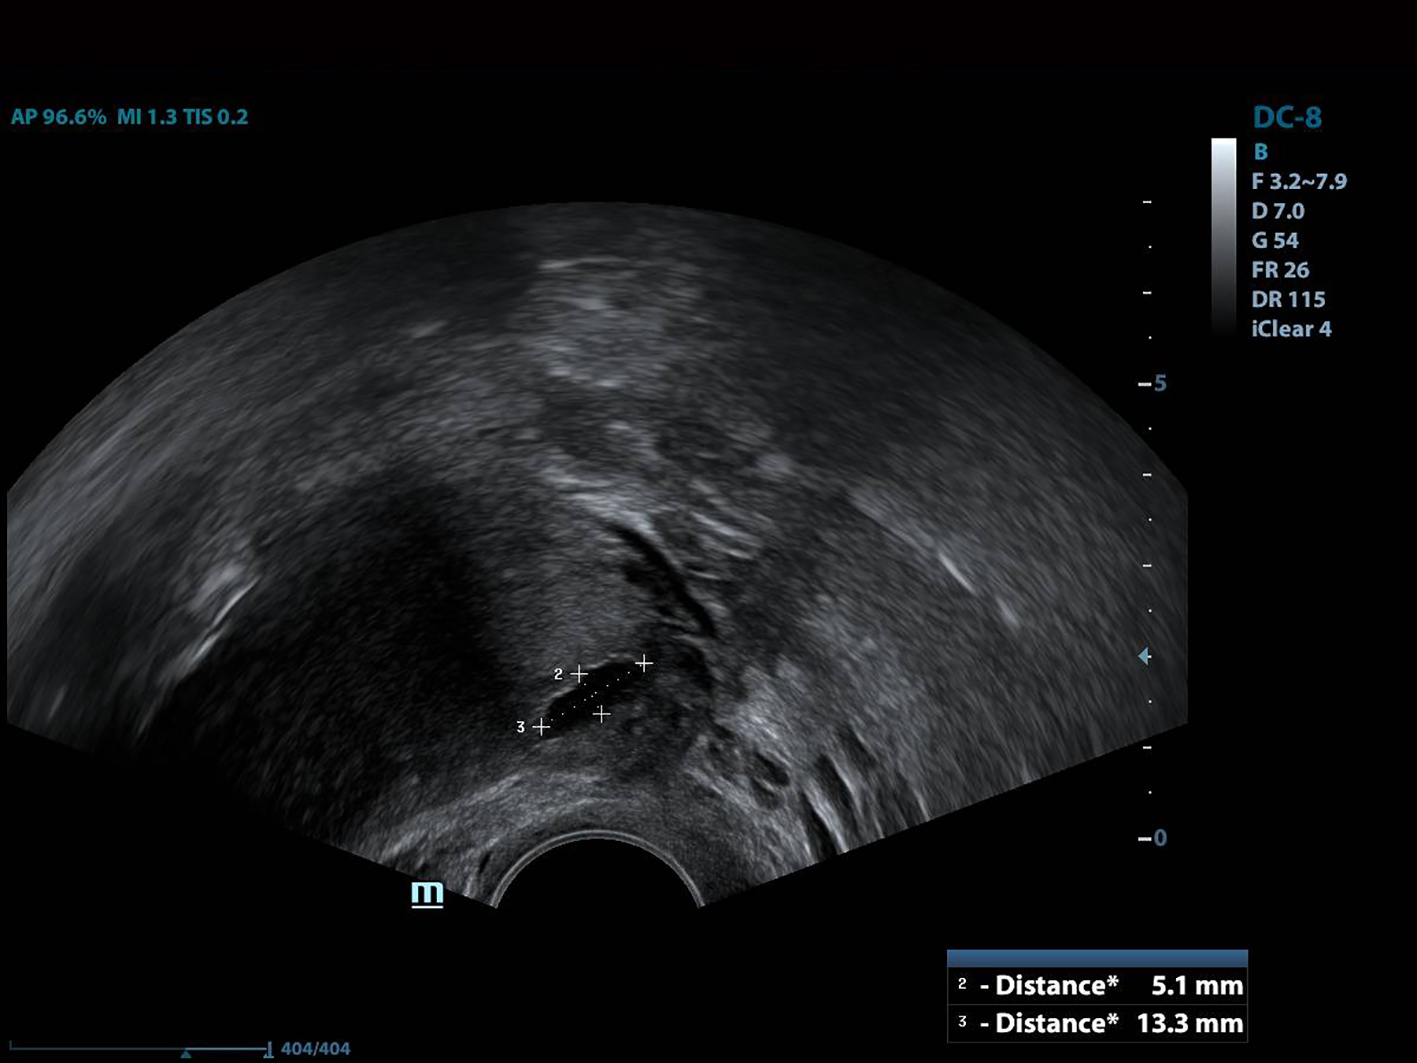

All of the patients underwent GnRh antagonist treatment. Ovarian stimulation with recombinant follicle stimulating hormone (FSH) was started on day 2 of menstruation. When the leading follicle exceeded 14 mm in length, a gonadotropin antagonist (Cetrotide, 0.25 mg; Merck, Kenilworth, NJ, USA) was started and human chorionic gonadotropin (hCG; Ovitrelle, 250 µg; Merck) was administered when there were at least two follicles > 18 mm in length. Transvaginal ultrasound-guided follicular aspiration was performed at 36 h after hCG injection. All women underwent transvaginal ultrasonography on the trigger day. The height, depth and width of the isthmocele were measured, and the volume was calculated (Figs. 1, 2). Residual myometrial thickness was also measured on the same day. Ultrasonographic images were taken of each patient. The embryos were frozen at 3 days after the intracytoplasmic sperm injection procedure. The depot GnRH agonist leuprolide acetate (3.75 mg; Lucrin Depot, Abbott, Istanbul, Turkey) was administered to all patients on day 1 following three consecutive months. Oral estrogen (Estrofem, three times daily) treatment was started at 20 days after the last GnRH analog dose. When the endometrium became suitable for embryo transfer, the isthmocele volume was remeasured and new ultrasonography images were acquired (Fig. 3). Embryo transfer was performed at 3 days after progesterone administration. A pregnancy test was performed on day 12 after embryo transfer. The pregnant patients were followed up and infants were delivered by cesarean section. All patients were managed by the same clinician.

![]() Click for large image | Figure 2. The depth of the isthmocele measurement. |

![]() Click for large image | Figure 3. The view of the isthmocele before embryo transfer. |